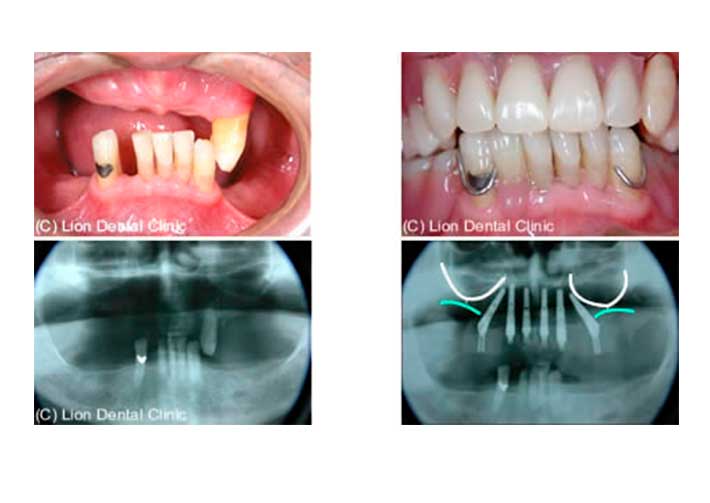

手術前

手術前の状態です。上の顎には歯が一本残っていますが、ぐらぐらです。

手術開始から3時間後

インプラント手術開始からわずか3時間で右のような固定性の義歯を入れることが可能です。

右下の写真で白い線が上顎洞のラインで青い線が歯槽骨の頂点のラインです。左右とも白い矢印のところでは3mmくらいしか骨がありません。ここに骨を作る治療方法もありますがその場合には歯が入るまでに半年以上かかってしまいます。